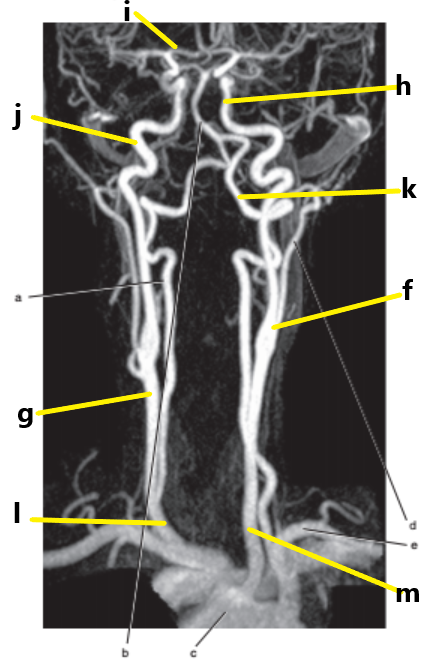

What is letter l ?

Common carotid

What is letter e ?

Subclavian artery

What is letter f ?

Common carotid artery

What is letter i ?

Anterior cerebral artery

What is letter m ?

What is letter j ?

Internal carotid artery

What is letter g ?

What is letter a ?

Vertebral artery

Aortic arch

What is letter b ?

What is letter d ?

External carotid artery

What is letter h ?

Internal jugular vein

What is letter k ?

Carotid bifurcation is -

superior border of thyroid cartilage

The common carotid artery bifurcates at the level of -

C3-C4

Carotid sinus/bifurcation